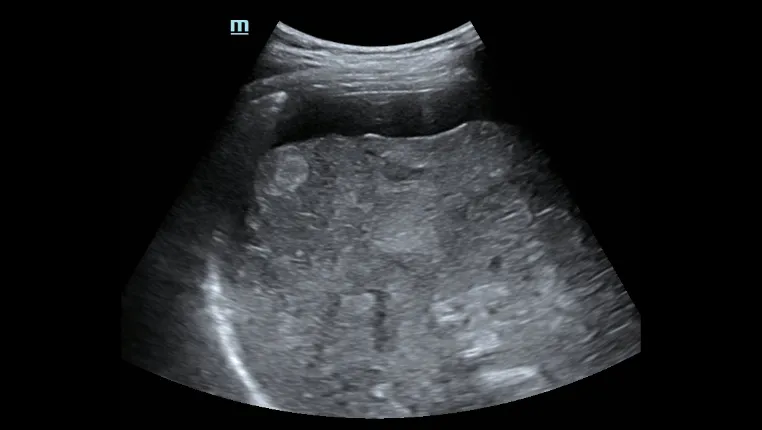

Пункция печени под контролем ультразвука